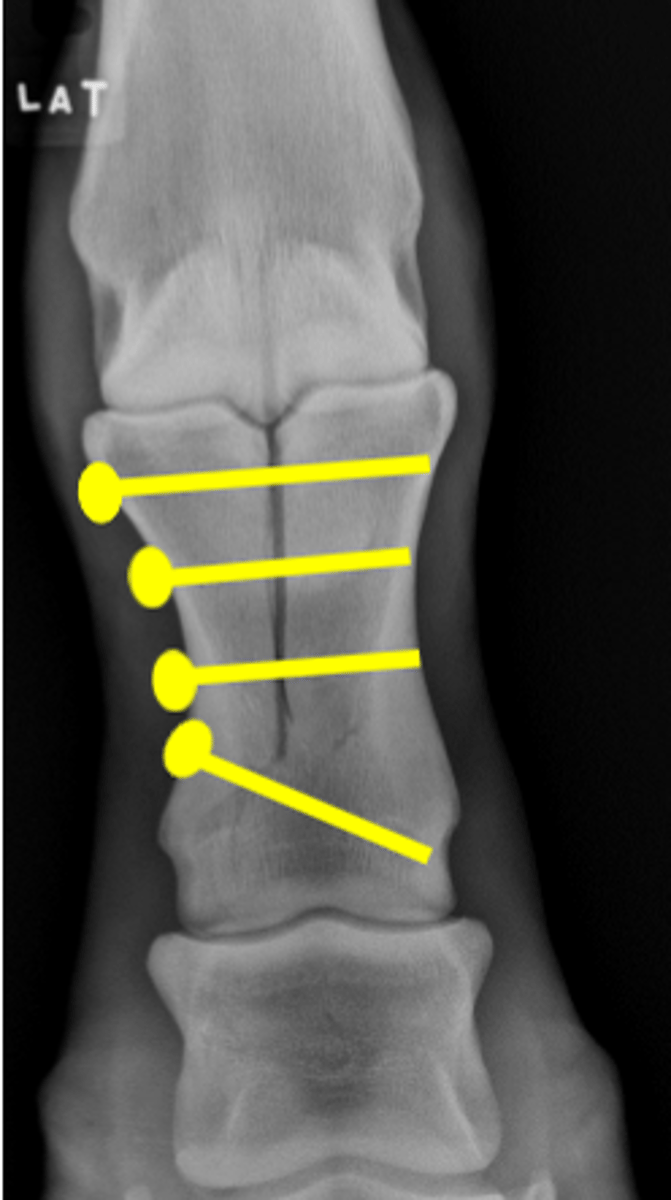

Osteochondral fragment

What is the radiology term for this lesion?

Arthroscopy

What is the preferred treatment for this lesion?